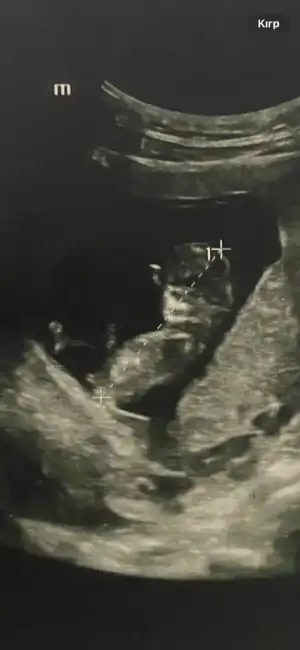

Annenin içine doğan olur genellikle, benim size cinsiyet tahminim de kıızBen hep kız hissettim hiç beklemiyordum açıkçası sürpriz oldu bana daama detaylı ultrason da farklı çıkabiliyormus onu da bir bekleyelim dedi doktor değişme ihtimali olur mu hiç bilmiyorum ama

Doktor çok emindi aslında kesin dedi ama ben emin olamayınca öyle dedi bakalım sağlıklı olsun daAnnenin içine doğan olur genellikle, benim size cinsiyet tahminim de kıızilk başta erkek diye yanlış yazmışım